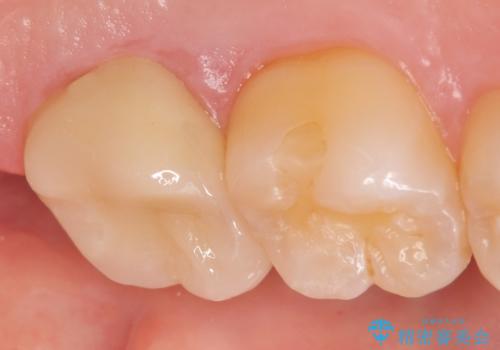

症状の緩解を確認後、オールセラミッククラウンによる補綴を行いました。

今回用いたオールセラミッククラウンはジルコニアフレームという白い素材の上にセラミックを盛っているため、審美性が非常に高いのが特徴です。

また、ジルコニアは人工ダイヤモンドの材料にも使われているほど高い強度を持っており、そのためオールセラミッククラウンは審美性だけでなく、奥歯やブリッジの補綴も可能とするクラウンです。